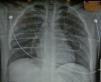

Radiografía de tórax normal.

Radiografía del tórax normal.

Con estos resultados decidimos iniciar la fase clínica y realizamos el primer trasplante pulmonar con un donante en asistolia extrahospitalario mediante «preservación en bitermia» en junio de 2010 a una paciente de 49 años con déficit de alfa-1 antitripsina. Realizamos un trasplante bipulmonar con éxito, con una magnífica función pulmonar tras más de 12h de isquemia total. Desde entonces, entre junio de 2010 y julio de 2011 hemos valorado 15 donantes en asistolia. La radiografía del tórax fue normal en 6 donantes (40%) (fig. 2), presentaban infiltrados pulmonares 7 donantes, en uno la radiografía era de mala calidad y en otro no se pudo realizar. La broncoscopia fue normal en 8 donantes (53%), 3 presentaban abundantes secreciones hemáticas en la vía aérea y en 2 había datos de broncoaspiración.